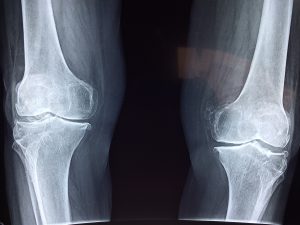

Entdecken Sie Chondroitin zur Förderung der Gelenkgesundheit, Linderung von Gelenkschmerzen und zum Schutz des Knorpels. Ideal für…

Erleben Sie die Vorteile von Glucosamin für gesunde Gelenke und Knorpel. Ideal für Menschen mit Arthrose oder…